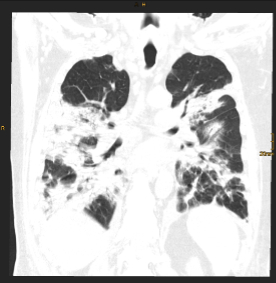

Pressebilder frei zum Download: ©Univ.-Klinik für Radiologie Innsbruck

BU: CT Thorax eines Teilnehmers während des stationären Aufenthalts (Bild links) und nach einem Jahr (Bild rechts) im Vergleich. Die initial ausgeprägten Gewebsvermehrungen sind deutlich rückläufig, jedoch zeigen sich residuell noch feine lineare Verdichtungen in beiden Unterlappen.

Eine aktuelle, kürzlich im angesehenen Fachjournal Radiology veröffentlichte Ein-Jahres-Folgestudie des Teams um den Radiologen Gerlig Widmann liefert nun neue Erkenntnisse zum Verlauf von Lungenveränderungen in der Computertomographie (CT) nach COVID-19. „In unserer viergeteilten Kohorte* betreffend den Schweregrad des initialen Verlaufes waren bei mehr als der Hälfte der Teilnehmer:innen auch noch zwölf Monate nach Krankenhausentlassung subtile Veränderungen im CT nachweisbar. Auch wenn eine Mehrheit dieses Anteils zumindest schwer erkrankt war, sind wir von diesem Ergebnis doch ein wenig überrascht. Der über 60-jährige männliche Patient mit kritischem Krankheitsverlauf trägt unseren Untersuchungen zufolge jedenfalls das größte Risiko, auch ein Jahr nach Covid-19 noch Lungenveränderungen im CT zu zeigen“, erklärt Radiologin und Erstautorin Anna Luger. Insgesamt wurden vier CT-Verlaufskontrollen der Lunge durchgeführt, von anfangs 142 Proband:innen konnten nach einem Jahr noch 91 Teilnehmer:innen in die Studie eingeschlossen werden.

Im Detail zeigten 34 Prozent der Teilnehmer:innen oberflächennahe netzartige Verdichtungen der Lunge, geringe Milchglastrübungen oder beides, bei 20 Prozent der Teilnehmer:innen waren ausgedehnte Milchglastrübungen, oberflächennahe netzartige Verdichtungen, Bronchialerweiterungen und mikrozystische Veränderungen feststellbar, die eventuell auf Vernarbungsprozesse hindeuten. „Aus radiologischer Sicht lässt sich noch nicht abschätzen, wie sich diese strukturellen Lungenveränderungen zeitlich weiter verhalten“, so der Leiter der Radiologie in der interdisziplinären Studiengruppe, Gerlig Widmann. Drei Szenarien seien jedoch vorstellbar: Die Veränderungen bilden sich langsam vollständig zurück, die Veränderungen halten an und es entwickeln sich stabile Vernarbungen, oder das Lungengewebe wird zunehmend fibrotisch (Bindegewebsvermehrung) und es kommt begleitend zu kontinuierlich zunehmenden klinischen Symptomen. „In jedem Fall“, so Widmann, „werden wir den Verlauf gemeinsam mit unseren klinischen Partnern weiter wissenschaftlich begleiten“.